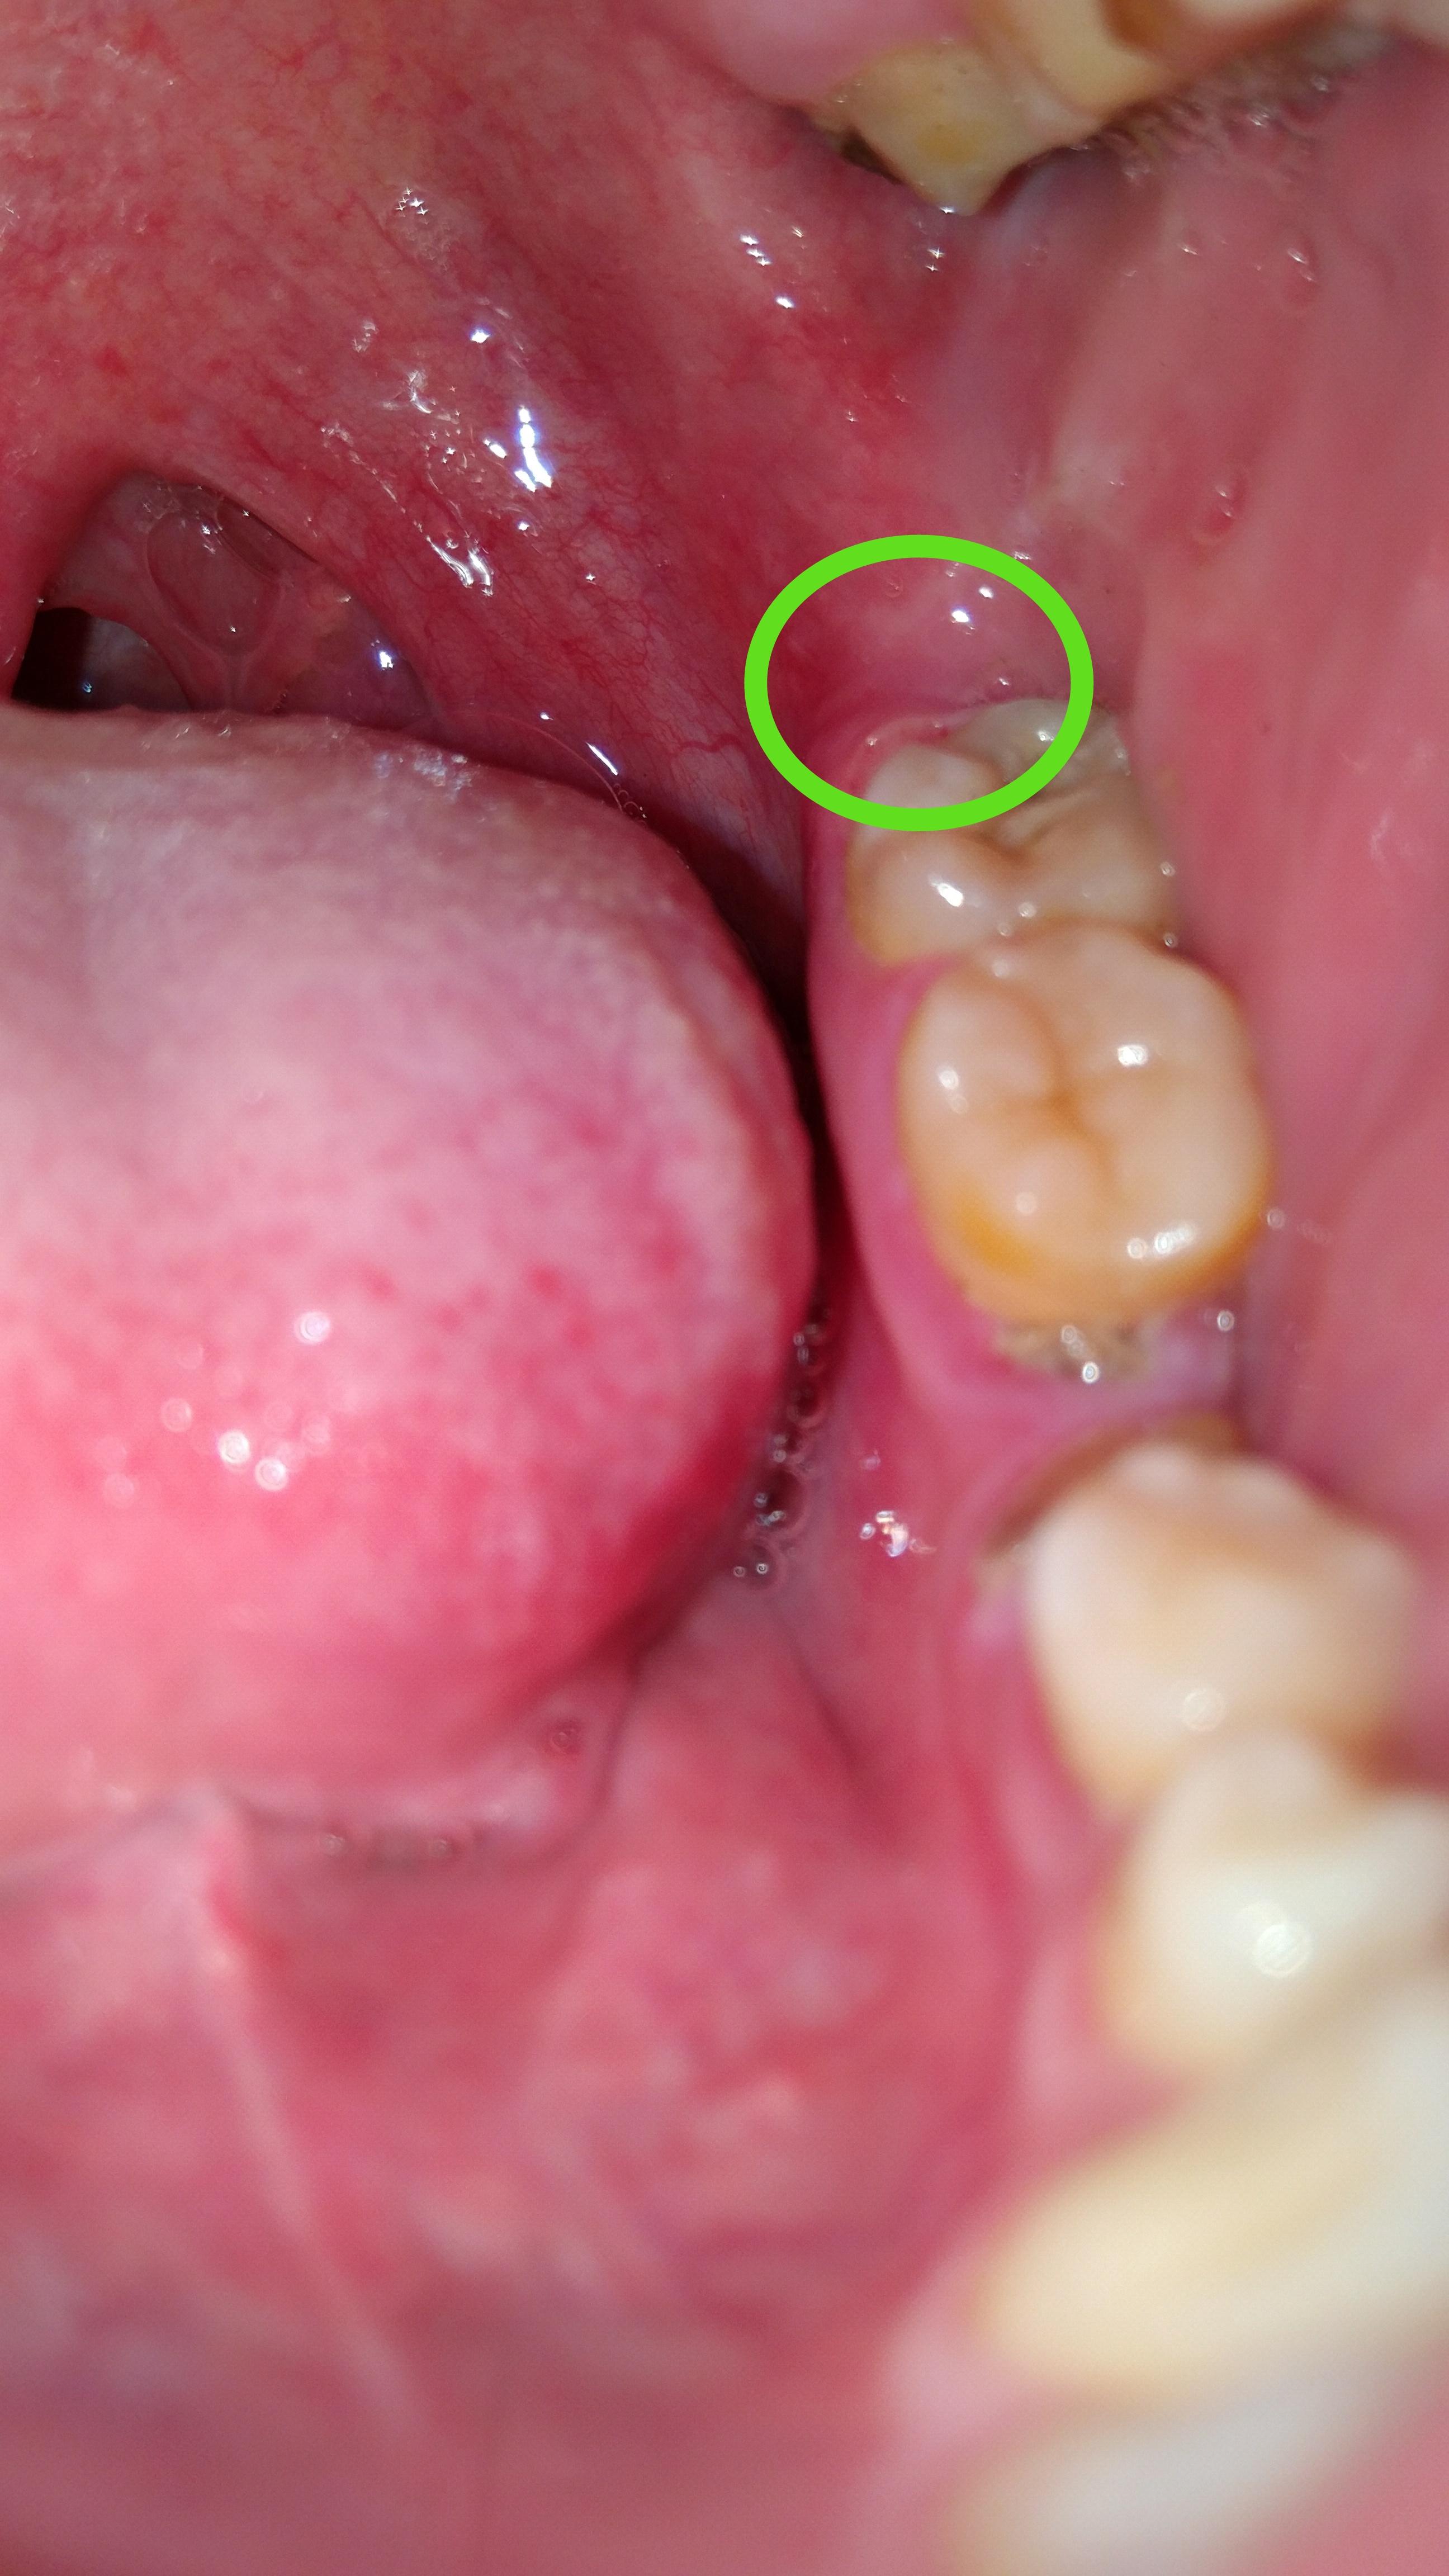

最开始左边牙齿最里面的那一颗有些不舒服,而后牙齿周边发疼,现在最里面的肉都非常疼,动嘴就疼。用药酒点了一下,更疼,舌头舔到好像起褶起

用手机开闪光灯拍了一下牙齿。图一图二,这样是智齿冠周炎吗?